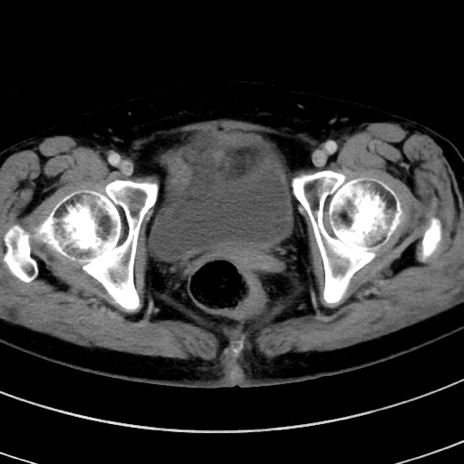

症例9(横断像)

【症例】 60歳代女性

【主訴】むかつき、みぞおちの痛み

【現病歴】3日前よりむかつきがあり、食事がとれない。

【既往歴】糖尿病

【身体所見】発熱なし、心窩部圧痛軽度あるも、腹膜刺激症状なし。

【データ】WBC 7400、CRP 1.92